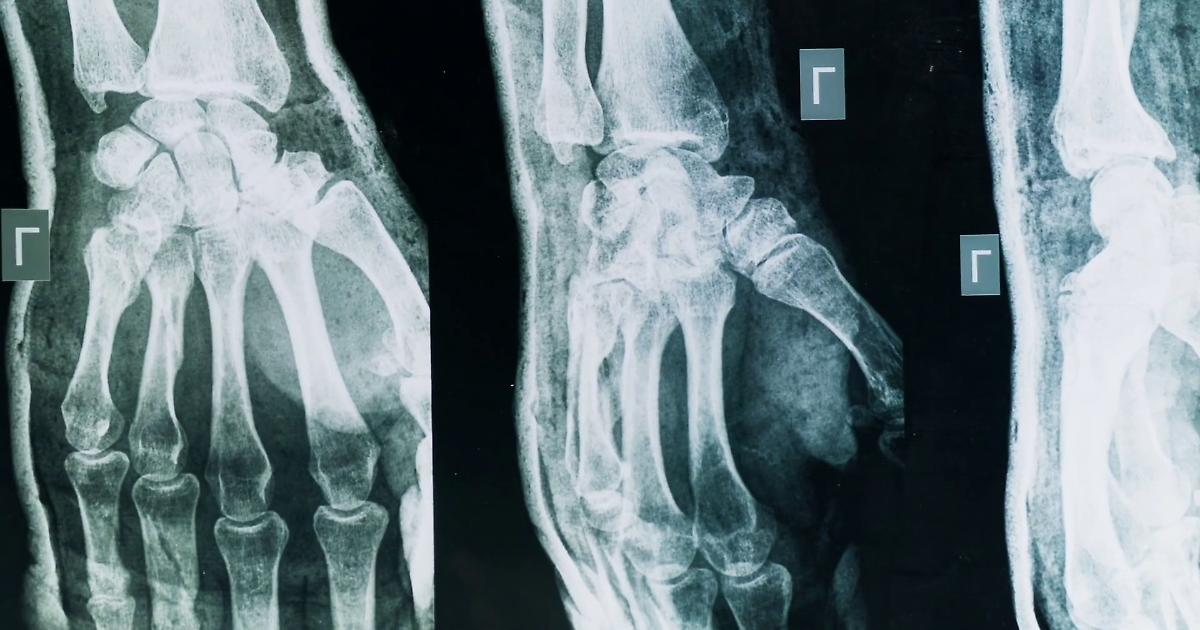

Artrite e artrosi, come riconoscerle e curarle